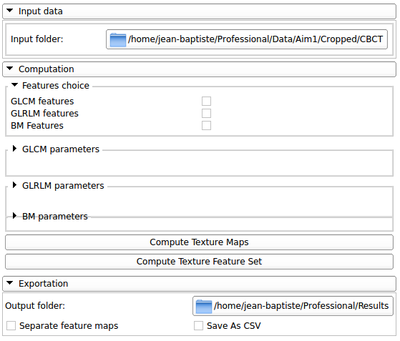

This extensions contain several modules that can be used to compute feature maps of N-Dimensional images using two well-known texture analysis methods: the study of Grey Level Co-occurrence Matrix (GLCM) and the study of Grey Level Run Length Matrix (GLRLM). The main algorithms used in this extension are part of a remote module of ITK called itkTextureFeatures Key Features:

Main modules interface

Input example

Texture features

Texture feature maps